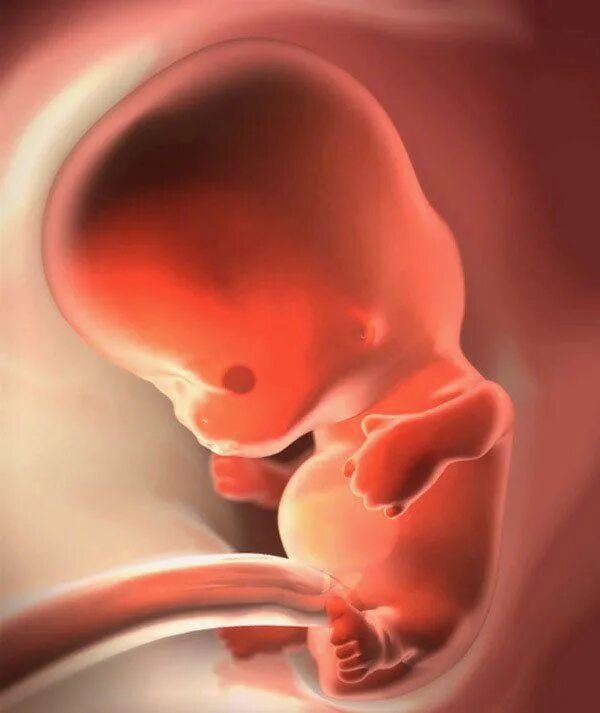

Как выглядит ребенок в 8 недель